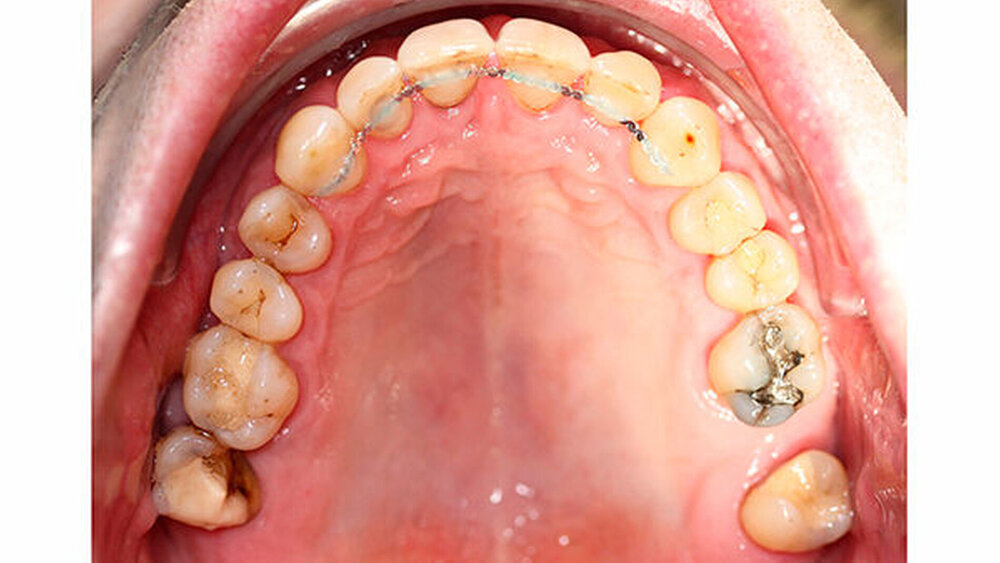

Intraoral zeigte sich ein bereits konservierend versorgtes permanentes Gebiss mit aktivem und inaktivem kariösen Geschehen. Große Anteile der Zahnhälse lagen nach Zahnfleischrückgang in Kombination mit Knocheneinbrüchen frei. Zahn 27 wurde bereits extrahiert.

Eine Beurteilung der parodontalen Situation an Zahn 11 offenbarte mesial und distal Sondierungstiefen von jeweils 6 mm.

Kieferorthopädisch imponierte beidseits eine neutrale Verzahnung bei einem tiefen Biss von 5 mm - bedingt durch die Verlängerung beider Frontzahngruppen. Besonders Zahn 11 zeigte eine erhebliche Verlängerung und Protrusion mit einer sagittalen Frontzahnstufe von 5 mm. Sowohl die Frontzähne im Ober- als auch im Unterkiefer wiesen eine lückige Beziehung zueinander auf (Abbildung 1).